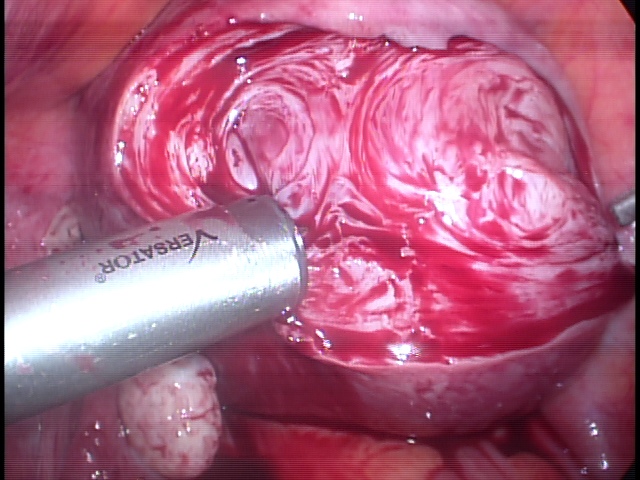

Procedimento cirúrgico que consiste na retirada de mioma intramural (localizado na parede do útero) ou subseroso (localizado fora do útero). Mioma submucoso (localizado dentro do útero) de grande volume também pode ser retirado através de laparoscopia evitando assim, um segundo tempo cirúrgico, como pode ocorrer na via histeroscópica.